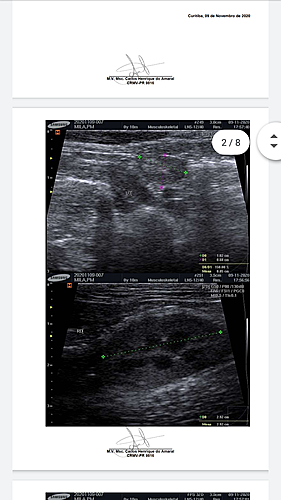

Diante da situação, corri com ela para uma segunda clínica veterinária, para ouvir uma segunda opinião e o veterinário me indicou a ida urgente ao Hospital Veterinário da região e onde foi realizado o exame de ultrassom e raio-x, novamente, e a Triagem Felina. A partir do resultado deste último exame, foi possível descobrir que a minha gatinha está com Leucemia Felina (FELV). Em decorrência desse quadro, a Mila terá que tomar antivirais, bem como se submeter a transfusões sanguíneas, tendo em vista o grau de anemia que a mesma se encontra, em virtude da doença.